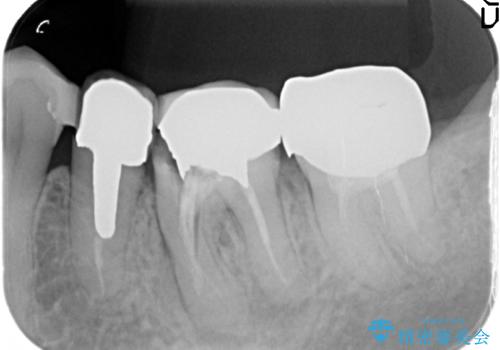

X線写真・視診より歯の破折クラウン下の虫歯再発が認められます。

クラウンの除去・虫歯の除去、根管治療を行ったのち、上顎は強い咬合力に対し破折抵抗性のある咬合面をメタルにしたメタルボンドによる補綴を計画します。

噛む力が甚大な場合、補綴物が破折したり場合により支台となる歯が破折してしまうことがあります。